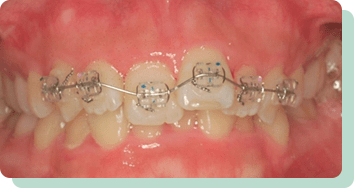

前歯の数本だけにワイヤーを当てて矯正治療を施すことで、前歯がキレイに並ぶケースなどもあり、比較的、短期間で費用を抑えて治療することが可能です。

また当クリニックでは、ワイヤー矯正、マウスピース矯正(インビザラインIGO)での部分矯正治療を取り入れています。

③器具が目立ちにくく、ケアしやすい

CASES